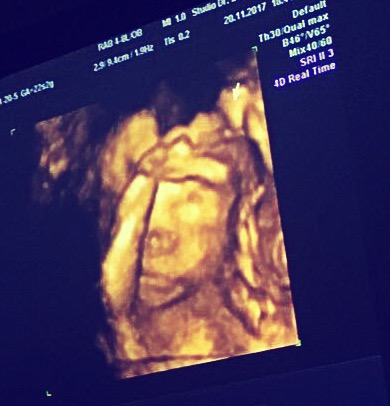

Una tappa importante e inquietante al tempo stesso di una gravidanza, immagino sia ecografia morfologica.

Dove il vostro bambino é un incrocio tra un modellino di pongo e l’urlo di Munch. Ma anche in questo passaggio ci saranno persone che sapranno già dirvi a chi assomiglia:

- guaaaarda, ha due occhi grandi proprio come il papàààà – (avesse già una terza di seno sarebbe più facile cogliere le somiglianze)

- ma guaaarda come tiene la manina davanti al viso, é timido come la sua mammaaa (nonono, mette la mano sulla faccia perchè già prevedeva il fiume di cagate e non voleva farne parte)

- il naso é tutto il tuo, spiccicato! (guarda, al massimo il naso é del chirurgo, però magari per osmosi se l’è già rifatto anche il feto)

Non mi sono ancora messa a pensare “chissà cosa prenderà da me, chissà cosa dal coinquilino”, capelli ricci/lisci, occhi verdi/palude, fisico aitante/aitante. Scherzando, dalla morfologica noi abbiam visto come primo elemento prorompente il naso, al che io e la zia Giada abbiamo deciso (nel caso fosse femmina) di regalarle una rinoplastica per i suoi 18 anni. Il coinquilino mi ha dato della “stronza”, bah, valli a capire ‘sti uomini.